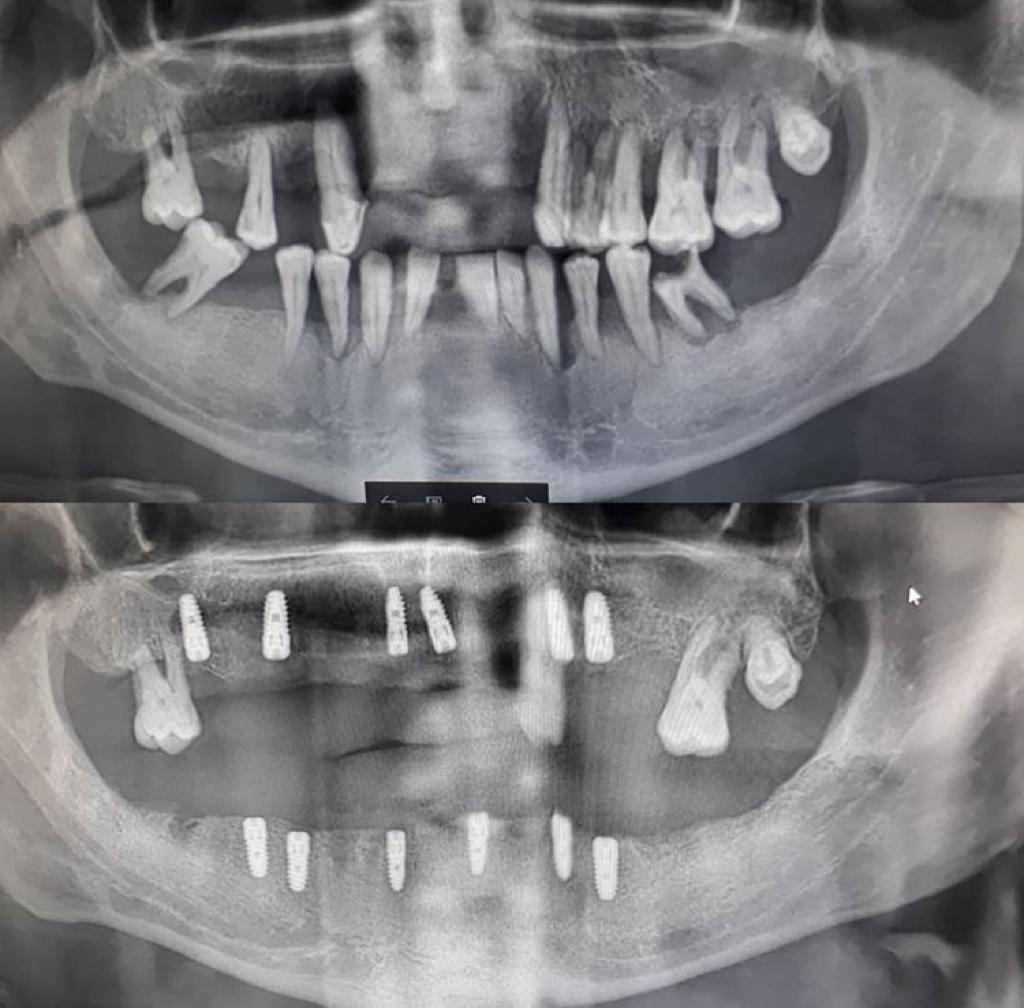

Özgül Dent Ağız ve Diş Sağlığı Polikliniği

Bitlis Özgül Dent Ağız ve Diş Sağlığı Polikliniği olarak yaptığımız örnek çalışmaları sizlerle paylaşarak fikir sahibi olmanızı sağlıyoruz. Sizde hizmetlerimizden faydalanmak için bizi arayıp randevu alabilirsiniz.